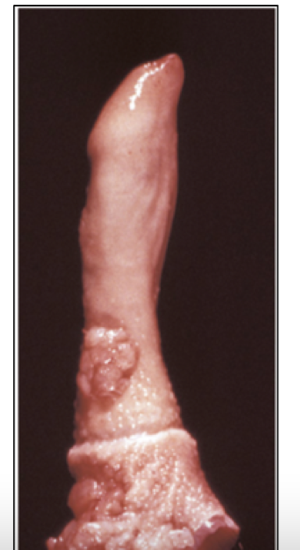

What is the likely cause of this lesion?

Canine TVT